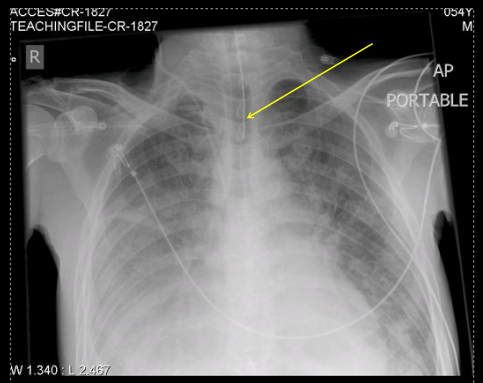

what type of tube is this?

ET tube